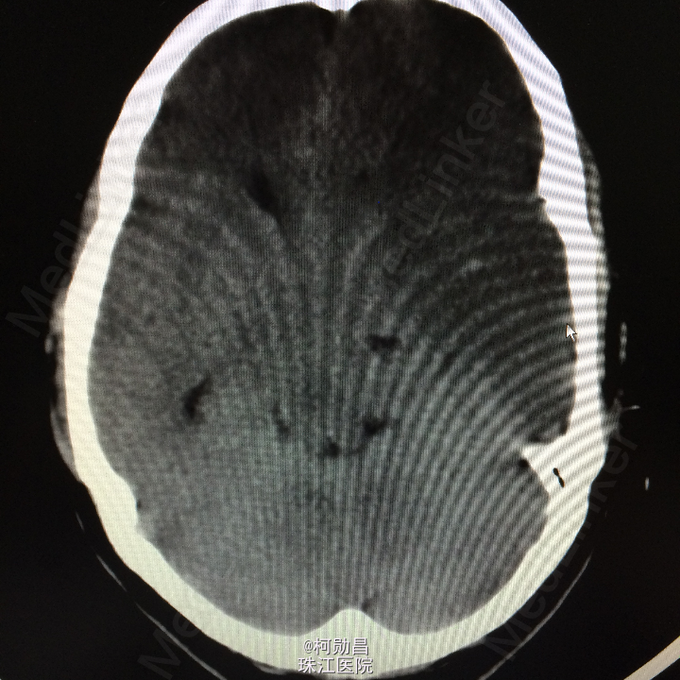

主诉:突发言语不能伴右侧肢体无力1天余 病史:患者于1天前无明显诱因突发言语不能,伴右侧肢体无力,表现为右侧肢体不能自主活动,无头痛头晕,无恶心呕吐,无肢体麻木、四肢抽搐、意识不清等症状。于当地医院就诊,查头颅CT提示:未见异常,予对症支持治疗,症状无好转。半天前患者症状加重,出现神志不清,呈嗜睡状态,现患者为求进一步诊治,遂至我院。门诊拟以“大面积脑梗塞”收入院。

查体:神志呈昏睡状态,言语不能,精神差,双侧瞳孔不等大,左侧3mm,对光反射消失;右侧瞳孔2,mm,对光反射灵敏,右侧肢体肌力0级,左侧肢体肌力5级,右侧肢体肌张力减低,余未见异常。 辅助检查:左侧大脑半球累计岛叶、基底节区(以颞顶叶为主)大片状低密度影,考虑脑梗塞;中线结构明显右移。

诊断:大面积脑梗 处理:予对症支持治疗,运用抗血小板治疗,抗凝治疗